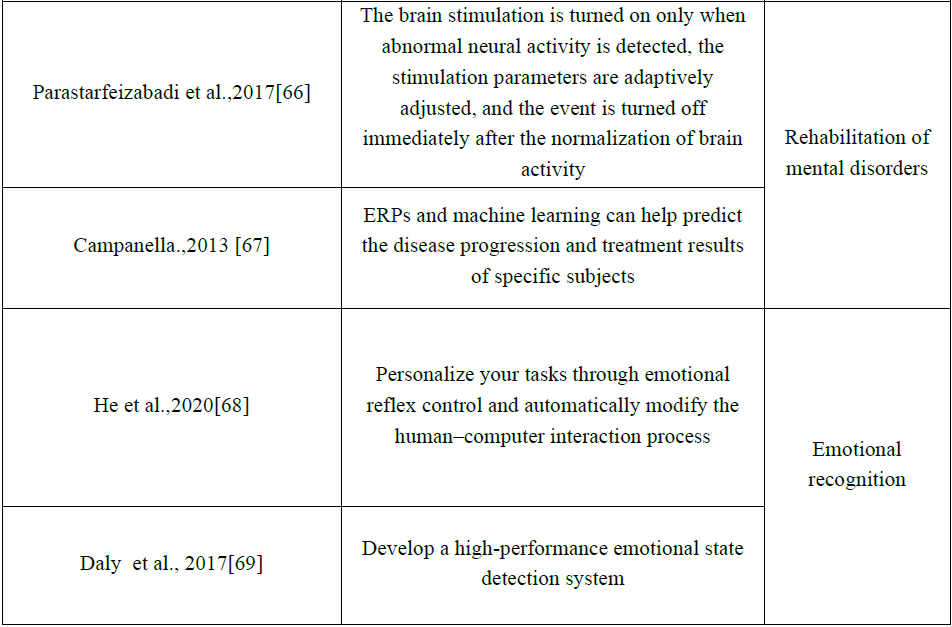

4 个性化BCI应用

不管是实验范式的个性化、脑信号处理的个性化还是神经反馈的个性化,其最终目的都是搭建BCI系统平台并投入到实际的应用中。在这个部分中,我们将探讨个性化BCI在运动功能障碍康复、精神疾病治疗康复、情绪识别等领域的应用。表3中列出了迄今为止主要的个性化BCI应用,同时本章将对表中内容进行评述。

Table 3 Different applications of personalized BCI

4.1 个性化BCI在辅助控制中的应用

目前BCI在辅助控制方面应用最多。其中BCI在通信与控制、运动替代等方向已经得到了大量的研究以及较为广泛的应用。

1)通信与控制

无论是BCI的通信还是控制,其基本原理都是类似的,都是通过识别特定模式的大脑信号,实现对外部指令/符号的输出。通过 BCI,严重残疾的用户可以与其他人进行交流,并对外部环境进行控制。Abiri等设计了一个基于手势控制的社交机器人[60],通过与神经反馈机制相结合,为用户定制解码模型以控制社交机器人的手势。Uma,M等开发的了一个个性化的GUI应用程序与EEG设备协作以满足用户的需求[43]。Abiri等证实,在光标控制中,个体的可视化能力与其光标的可控性水平之间存在正相关关系,这可以为个性化的光标控制提供方向[70]。

2)运动替代

AnnalisaColucci等在2022年发表的文献中提到[71],将大脑/神经活动转换为可穿戴执行器的控制信号,能够让大脑/神经外骨骼(B/NE)在运动功能受损的情况下执行运动。在个性化BCI中,Coscia M等[61]通过监测预测精神疲惫的生理生物标志物,例如心率变异性、皮肤电反应或呼吸频率,根据患者的个体能力进行调整改善B/NE的控制参数。此外,Vinoj等人开发了可以根据残疾程度进行个性化定制[62]下肢外骨骼(brain-controlled lower limb exoskeleton BCLLE)。

4.2 个性化BCI在神经疾病康复中的应用

下面以帕金森(Parkinson disease, PD)和脑卒中后的治疗康复为例,讨论个性化BCI在运动与认知功能障碍康复领域的应用。

1)帕金森病的治疗康复

目前还没有能完全治愈帕金森病的方法[72],个性化BCI有望使帕金森病患者的症状有所好转。Bronte-Stewart H M等利用双向深部脑机接口(bidirectional deep brain-computer interface ,dBCI)提出了个性化双阈值控制策略,并将该策略应用于神经或运动输入,以驱动闭环丘脑底核深部脑刺激 (subthalamic nucleus - deep brain stimulation STN-DBS ),用于治疗帕金森病[63]。这是一种个性化的BCI,与传统BCI不同,其根据特定用户的活动状态和用药周期无缝地调整神经刺激的参数,目的是为特定的帕金森病患者提供治疗康复效果最佳的参数,该研究首次证明了闭环深部脑刺激(Deep brain stimulation ,DBS)对PD可行性和有效性。

2)脑卒中后康复

脑卒中会导致患者认知障碍或/和运动障碍[73],针对这两种障碍的康复,当前个性化BCI主要利用基于BCI的神经反馈训练以及经颅电刺激(transcranial electrical stimulation TES)进行干预。

(1)认知障碍康复

研究发现增加特定EEG频带的能量可以改善认知表现,Kübler A等利用该发现设计了基于BCI的神经反馈训练模块以增强脑卒中患者的认知功能,提出了一种神经心理学算法,根据神经心理测试结果,可以为特定脑卒中患者定制或分配不同的、最适合的神经反馈训练模块[64]。

(2)运动障碍康复

Mane R等采用经颅直流电刺激结合BCI(transcranial Direct Current Stimulation coupled BCI TDCS-BCI)对脑卒中患者上肢运动障碍进行干预,发现脑对称指标和功率比指标(Power ratio index PRI)是TDCS-BCI干预的最佳预测指标,这些预测指标有助于识别不同患者的生物特征标志[65]。可以利用特定患者的这种生物特征标志预测其对现有干预措施的预期反应,将预期收益最高的干预措施推荐给患者,从而实现个性化的康复方案。与传统BCI相比,这种个性化BCI应用解决了通用方案对不同患者的适应性问题,为每个患者提供适合自己的、预期收益更高的康复方案。

4.2 个性化BCI在精神障碍康复中的应用

以从大脑向外输出指令为主的BCI(输出式BCI)其功能主要实现与外部世界的通信与控制,与这类BCI相比,还有另一类 BCI,主要由外部设备或机器绕过外周神经或肌肉系统直接向大脑输入电(如DBS),经颅直流/交流电刺激(Transcranial direct/ alternating current stimulation,tDCS/tACS[74-76]))、磁(如经颅磁刺激(Transcranial Magnetic Stimulation,TMS))、声(如经颅超声刺激(Transcranial ultrasound stimulation,TUS))和光等刺激或神经反馈,以调节中枢神经活动,这类BCI可用于精神障碍的物理干预以促进康复。

输入式BCI对精神障碍的调节功效一个主要因素是对特定患者优化最佳神经调节或刺激参数,即个性化的刺激参数设置。Fellous, J.-M.等采用先进的机器学习算法识别大脑状态,并利用神经特征优化刺激参数,他们引入了可解释的人工智能(ExplainableArtifificial Intelligence XAI),以数据驱动的方式识别特定的生物特征标志(如事件相关电位(Event-related Potentials,ERPs)[76-79])来检测异常神经活动[80]。例如,在酒精成瘾患者和动物模型中观察到延迟和/或降低的ERP振幅[78,79,81,82]。当检测到异常的神经活动时开启对大脑的刺激,自适应调整刺激参数,并在大脑活动正常化后立即关闭刺激[66]。ERPs和机器学习可以支持精神症状的诊断,并对特定受试者的疾病进展和治疗结果进行预测,从而实现个性化的治疗康复[67,83]。

4.3 个性化BCI在情绪识别中的应用

情绪调节对个体的身心健康很重要,情绪识别是情绪调节的基础。不同个体的情绪会随时间和环境的变化而变化[84],因此,需要为特定个体定制BCI以识别情绪。

情感BCI (Affective BCI,aBCI)通过测量神经生理信号来监测情绪状态,帮助用户主动定制心理任务,以提高人机交互的性能[68]。例如,个体利用情绪变化操控游戏,当其意识到自己的情绪状态会影响游戏参数时,他会根据自己的偏好主动改变情绪,通过操控游戏的结果和情绪反馈对心理任务进行调整,实现基于个性化的aBCI操控游戏[85]。

此外, Daly等研发了一种用于音乐脑机接口(Brain-computer music interfaces,BCMI)的情绪状态检测系统[69],其中的BCMI通过音乐诱发用户情绪以帮助其调节情绪[37]。Daly 等针对每个受试者训练分类器(实验中使用的音乐刺激由情感算法作曲(Affective algorithm composition AAC)系统创作[86,87]),实验结果表明,与普通的BCIM相比(P<0.05),个性化的BCMI系统能够更准确地检测受试者的情绪(P<0.01)。